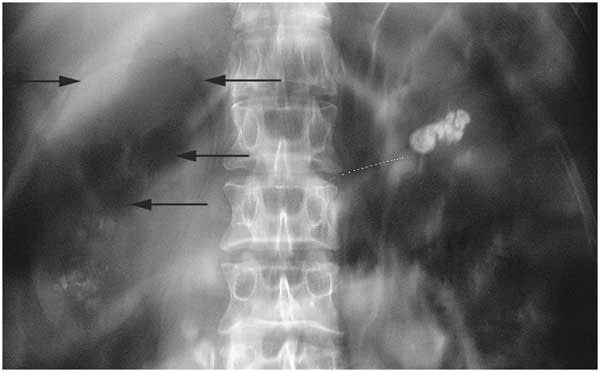

• 요로결석: 극심한 콕콕 쑤시는 듯한 통증, 혈뇨, 메스꺼움 동반

• 수신증(신장에 소변이 차는 질환): 뻐근하고 둔한 좌측 허리 통증

• 초음파 및 CT: 결석, 종양, 염증 등 병변 직접 확인